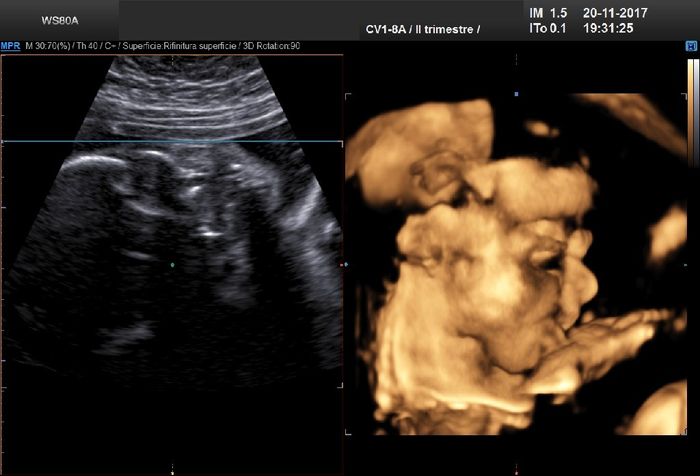

Ciao ragazze, io sono a 20+4 e due giorni fa abbiamo scoperto alla morfologica di aspettare un maschietto! Il nostro patato si chiamerà Diego, è lungo 26,2 cm per 380...